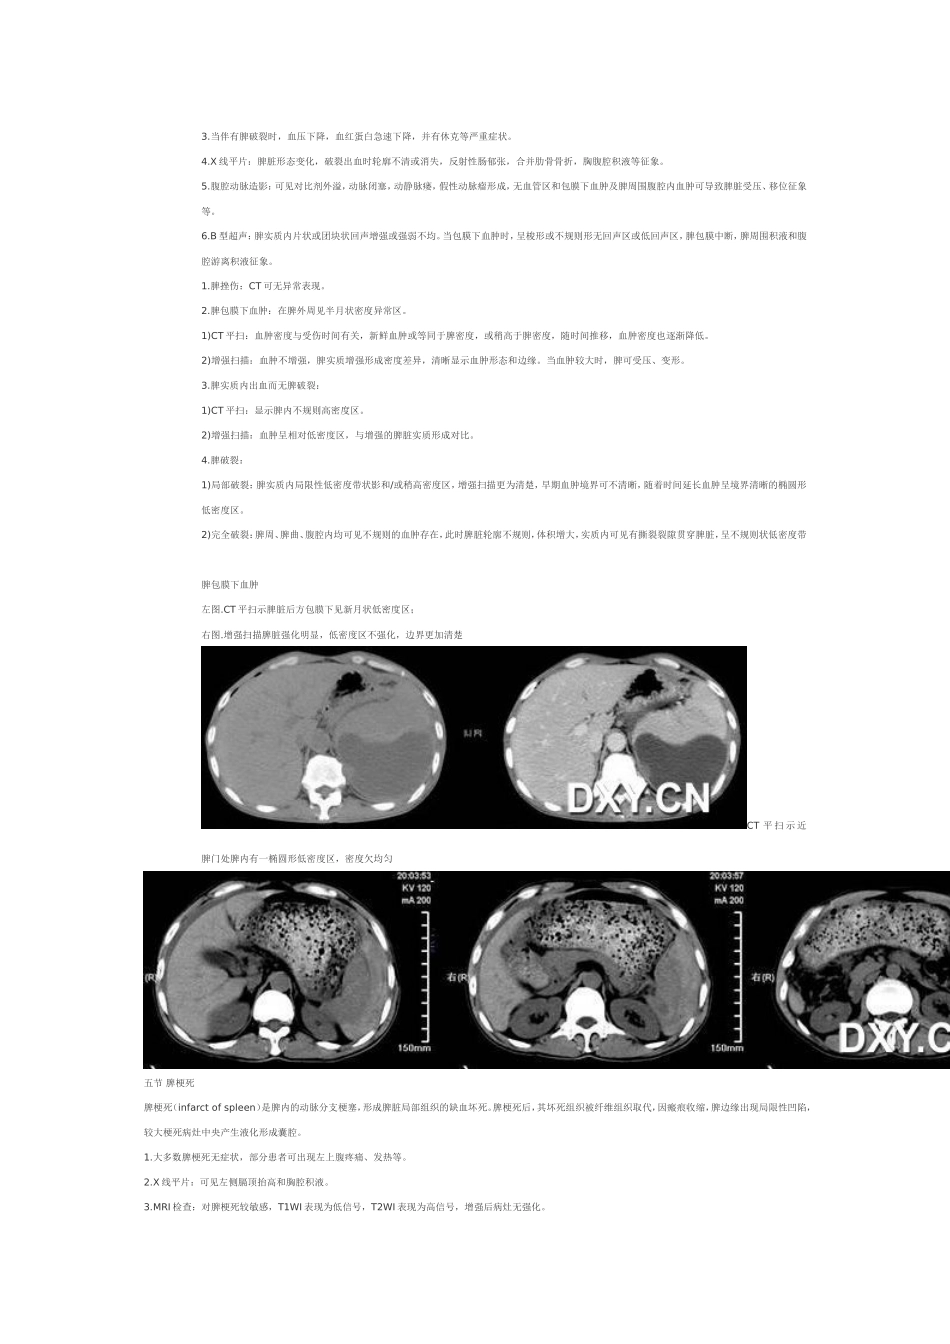

第一节脾肿大脾脏弥漫性疾病多表现为脾肿大(enlargedspleen)。脾脏大小个体差异较大,解剖学测量脾脏的平均长10.5cm,宽6.5cm,厚2.5cm,最大径超过15cm者肯定增大。引起脾肿大的病因很多,主要有炎症性、淤血性、增殖性、寄生虫感染、胶原病和浸润性病变等。诊断要点:1.症状和体征:1)部分患者无明显自觉症状。2)脾肿大病因不同而致临床症状各异。3)深吸气时,脾脏触诊在肋缘下超过2~3cm。叩诊时,脾浊音区相应扩大。2.X线平片:脾脏X线测量长径超过15cm,宽径超过8cm可诊断脾肿大。明显增大时可引起左膈升高,胃泡右移,左肾轮廓影向内下方移位。3.消化道钡餐造影:可显示脾大对胃肠道的压迫、推移征象,结肠脾曲下移,相应的横结肠上缘出现压迫。4.MRI检查:单纯性脾肿大MRI信号强度均匀。【CT表现】1.CT平扫:显示弥漫性脾肿大的程度、形态、实质密度变化及周围组织和器官的压迫推移征象。1)长径超过10cm,短径超过6cm,上下方向长度超过15cm即为脾肿大(图6-5-1A)。2)横断面图像上以5个肋单元作为标准,超过者为脾肿大。若肝下缘消失的层面上,脾下缘仍能见到则可认为脾向下增大(图6-5-1B)。3)当脾脏密度高于肝脏密度时,提示有肝脏弥漫性病变。2.增强扫描:动脉期脾脏呈斑片状不均匀强化,静脉期及平衡期强化密度逐渐均匀。弥漫性脾肿大超过5个肋单元第二节第二节副脾副脾(accessoryspleen)又称额外脾。为先天性异位脾组织,与主脾结构相似,具有一定功能的脾组织。约占尸检10%~30%,多为单发,常位于脾门或沿脾血管分布,也可沿脾脏的悬韧带分布。约有20%的副脾发生在腹部或后腹膜的任何地方。【诊断要点】1.症状与体征:通常无临床症状,较大者可于上腹部触及肿块。2.消化道钡餐造影:位于胃壁或胃周围者,可显示类似胃粘膜下肿瘤征象。3.MRI检查:形态上呈圆形或椭圆形,信号特征与主脾相同,增强扫描,副脾与主脾的强化一致。4.DSA检查:可见脾动脉的小分支进入副脾,与主脾染色一致。【CT表现】1.CT平扫脾门部小结节,多数直径不超过2.5cm,边缘光滑。偶见位于脾门以外者。2.增强扫描副脾与主脾强化一致,CT值相同。3.动态增强扫描:两者的增强与消退之动态变化也完全一致。4.鉴别诊断:需与腹部肿瘤鉴别,勿把副脾误认为淋巴结肿大或其他肿物。脾摘除后副脾可增大。副脾也可发生脾脏的病变,如淋巴瘤。左图:CT平扫示脾门处类圆形小结节影,边界光滑右图:增强扫描脾门部小结节影均匀强化,与脾脏强化一致第三节第三节多脾综合症多脾综合征(polyspleniasyndrome)为先天性脾脏发育异常伴有多个内脏畸形和心血管畸形的综合征。本病较为罕见。【诊断要点】1.多脾:多在2个以上,大小相近,位于双侧腹部或右腹部,脾总重量等于正常脾重量。2.心血管畸形:如肝段下腔静脉缺如,奇静脉或半奇静脉异常连接并扩张,肝静脉直接汇入右心房,双上腔静脉,双主动脉弓,房间隔缺损,室间隔缺损,单心房及心脏位置异常等。3.两侧肺分叶异常。4.内脏异位:可为部分性或完全性内脏转位。5.其他表现:如胆囊缺如,胆管闭锁等。【CT表现】1.多为两个或两个以上的脾脏,呈结节状或球状,其密度和增强扫描强化特征与正常脾脏相同。2.脾脏异位,可位于右侧腹部。3.复杂的心血管畸形及心脏位置异常等。4.肝左右叶反位或对称等大,胆囊缺如等畸形表现。左图:CT平扫示左上腹脾区有两个球形软组织密度影,边缘光整;右图:增强扫描两个球形软组织密度影均匀强化第四节第四节脾外伤脾外伤(traumaofthespleen)占腹部外伤的1/4。因受力机制不同,可为单纯性脾外伤,也可同时合并肝及其他器官和组织损伤。脾外伤的分型:①脾挫伤。②脾包膜下血肿。③脾实质内出血而无脾脏破裂。④脾破裂。【诊断要点】1.明确的左上腹创伤史。2.脾脏外伤后,可出现左腹部痛,脾脏增大,压痛以及腹膜刺激征象。3.当伴有脾破裂时,血压下降,血红蛋白急速下降,并有休克等严重症状。4.X线平片:脾脏形态变化,破裂出血时轮廓不清或消失,反射性肠郁张,合并肋骨骨折,胸腹腔积液等征象。5.腹腔动脉造影:可见对比剂外溢,动脉闭塞,动静脉瘘,假性动脉瘤形成,无血管区和包膜下血肿及脾周围腹腔内血...